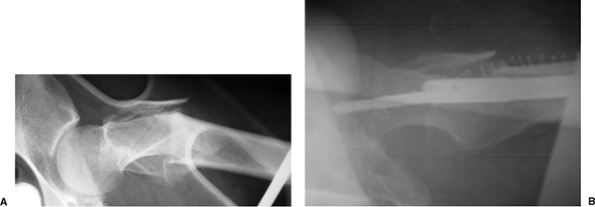

nondisplaced femoral-neck fracture that was treated with multiple

screws. Two months after the surgery, she fell again, sustaining a

subtrochanteric fracture. Her injury was revised with a piriformis

entry nail but in a malreduced position. After 1 year, her fracture was

successfully revised with a percutaneous osteotomy, autogenous bone

grafting with DBM extender, and TriGen Intertan (Smith & Nephew,

Memphis, TN) nailing in a reduced position with the channel reamer

technique (Fig. 20.48).

![]() |

Figure 20.48. A–C.

Preoperative nonunion of subtrochanteric fracture with malreduction of proximal fragment. Note poor bone apposition because of the malreduction. D,E. Postoperative appearance with percutaneous osteotomy and grafting with reduction of deformity and fixation through use of TriGen Intertan system. |